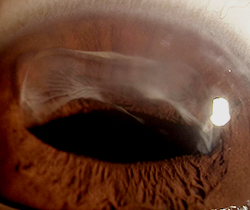

인공수정체의 위치 이상(인공수정체 탈구)

백내장 수술시 삽입했던 인공수정체가 정상 위치를 벗아난 경우를 말하며, 이탈된 정도에 따라 앞이 뿌옇게 보이고, 시력저하가 나타납니다.

야마네 고정술

수술 전

수술 후